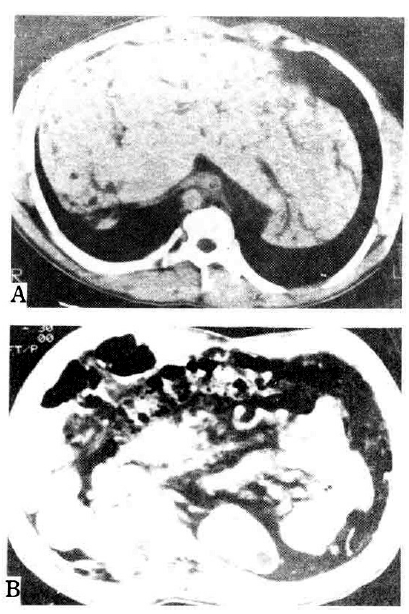

On admission to our hospital, the patient’s temperature was 39.3°C, the pulse 92, and the respiration 24. The blood pressure was 110/70 mmHg. On examination, the patient was relatively well-nourished but appeared acutely ill. No rash, lymphadenopathy, or jaundice was evident. The liver was 3 finger-breadth’s palpable on the epigastrium, which was hard and tender. The kidney was not palpable. We reviewed the microscopic findings of the obtained previous liver biopsy specimen, which had been done 3 years ago. Microscopic finding showed preserved normal hepatic cell cords with diffuse portal and periportal fibrosis surrounded by proliferated bile ductules and bizarre-shaped ectatic bile ducts (Fig. 1). Abdominal computed tomography findings revealed Caroli’s disease and hepatomegaly accompanied by multiple renal cysts (Fig. 2). We diagnosed him with congenital hepatic fibrosis and Caroli’s disease, complicated by cholangitis. As a result, due to suspicion of hereditary causes, we reevaluated and tested his family members, including the Case 2 and Case 3 patients. The laboratory and imaging findings are summarized in Table 1.

Abdominal computed tomography in case 1. A. Hepatomegaly with dilatation of the intrahepatic bile duct is demonstrated. The spleen is not seen due to previous splenectomy. B. Multiple cysts are noted in both kidneys.